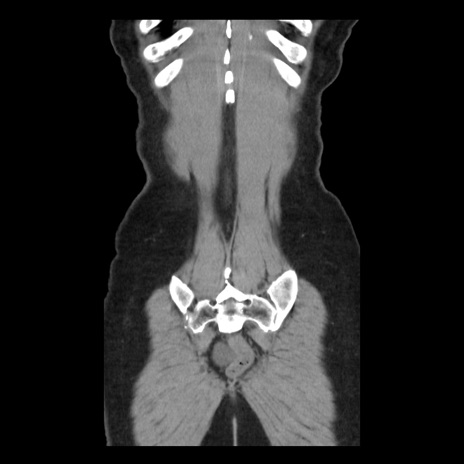

矢状断像